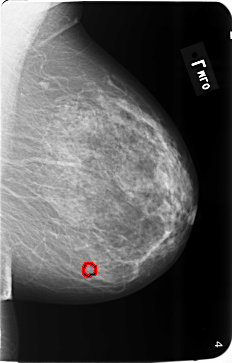

B_3493_1.LEFT_MLO

LEFT_MLO LINES 5800 PIXELS_PER_LINE 3712 BITS_PER_PIXEL 12 RESOLUTION 50 OVERLAY

FILE: B_3493_1.LEFT_MLO.OVERLAY

TOTAL_ABNORMALITIES 1

ABNORMALITY 1

LESION_TYPE CALCIFICATION TYPE PLEOMORPHIC DISTRIBUTION CLUSTERED

ASSESSMENT 4

SUBTLETY 3

PATHOLOGY BENIGN

TOTAL_OUTLINES 1

BOUNDARY